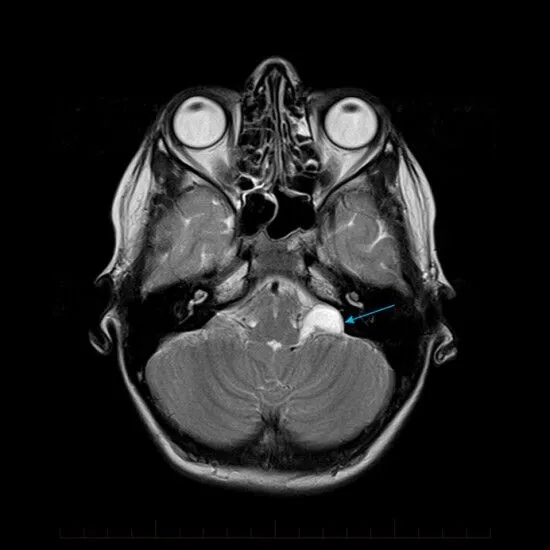

Máy MRI mà Trung Quốc dự định chế tạo sẽ tạo ra từ trường lên tới 14 tesla, đủ mạnh để kích thích các hạt nhân của phân tử nặng hơn như natri, phốt-pho và kali, giúp chụp được hoạt động của não bộ.

Một tế bào neuron thần kinh có đường kính khoảng 4 - 100 micromet, nhưng máy MRI mạnh nhất hiện nay chỉ có thể quan sát được vật thể đường kính nhỏ hơn 1000 micromet. Nếu dự án thành công, vật thể nhỏ cỡ 1 micromet cũng có thể quan sát được.